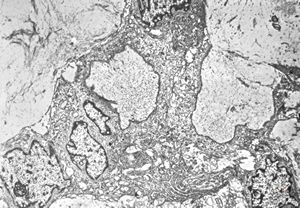

normal seromucinous salivary gland

oral saprophytic bacterium